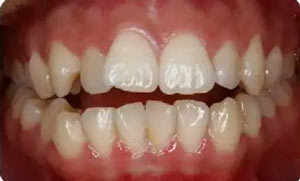

—上中線左偏,下中線右偏

—咬合平面右低左高

—前牙開(kāi)合

—右側(cè)磨牙近中關(guān)系,尖牙遠(yuǎn)中關(guān)系

—左側(cè)磨牙遠(yuǎn)中關(guān)系,尖牙近中關(guān)系

—前磨牙區(qū)及前牙區(qū)均為開(kāi)合

—右側(cè)自第一磨牙開(kāi)始至側(cè)切牙均為反合

Spee曲線1.5mm;前牙開(kāi)合3mm;深覆蓋4mm